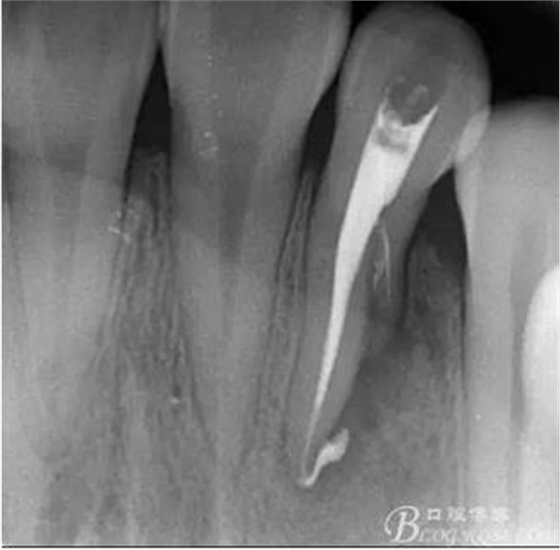

(6)復(fù)診:原暫封材料再位,牙周無明顯異常與不適,常規(guī)清潔根管,H銼清除根管內(nèi)維他,次氯酸鈉終末消毒,干燥根管,單尖測(cè)壓發(fā)充填根管,術(shù)后拍片到位。